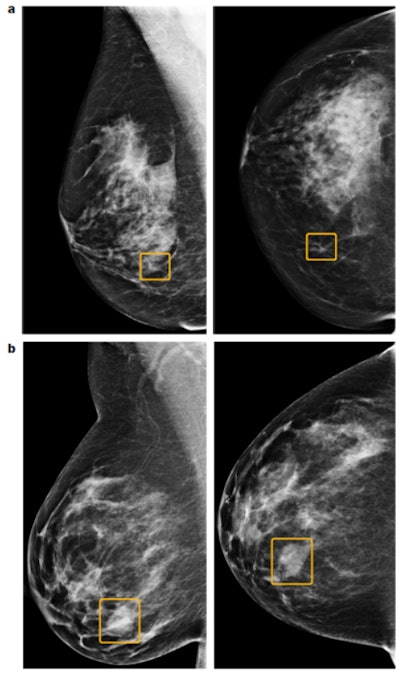

A Google Health study involving nearly 29,000 mammograms from the U.K. and U.S. has provided fresh evidence that artificial intelligence (AI) can be as effective as human radiologists at detecting breast cancer. The findings were published in Nature on 1 January.

Lead author Scott Mayer McKinney and colleagues from Google Health, DeepMind, Imperial College London, the U.K. National Health Service (NHS), and Northwestern University in Evanston, Illinois, U.S., developed a deep-learning AI model that could identify breast cancer on screening mammograms. They evaluated this system using data from almost 26,000 women examined at three NHS hospital groups as part of Optimam, an image database of more than 80,000 digital images extracted from the U.K. National Breast Screening System (NBSS).

This was a research study, not a clinical one, but AI correctly identified cancers from the images with a similar degree of accuracy to expert radiologists, and AI also reduced the proportion of screening errors, according to the authors. They reported a reduction of 5.7% and 1.2% (U.S. and U.K., respectively) in false positives, and a decrease of 9.4% and 2.7% (U.S. and U.K., respectively) in false negatives.